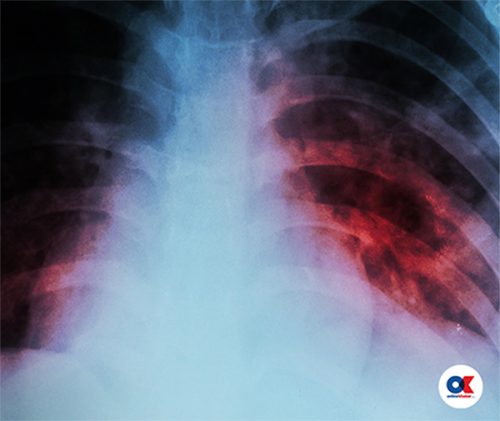

टिबी एवं क्षयरोगले शरीरको कुनैपनि भागलाई असर गर्नसक्छ । तर, धेरैजसो फोक्सो, घाँटी, हड्डी, पेट, मस्तिष्कमा यसको असर रहन्छ । क्षयरोगबाट सबैभन्दा बढी फोक्सो प्रभावित हुन्छ । ७० देखी ...

क्षयरोग एक व्यक्तिबाट अर्को व्यक्तिमा श्वासप्रश्वासको माध्यमबाट सर्छ । चिकित्सकीय भाषामा यसलाई ट्युबरकुलोसिस भनिन्छ । छोटकरीमा यो रोगलाई टीबी भनेर चिनिन्छ । क्षयरोग माइकोब्याक्टेरियम ट्युबरकुलोसिस नामक कीटाणुबाट लाग्ने एक...